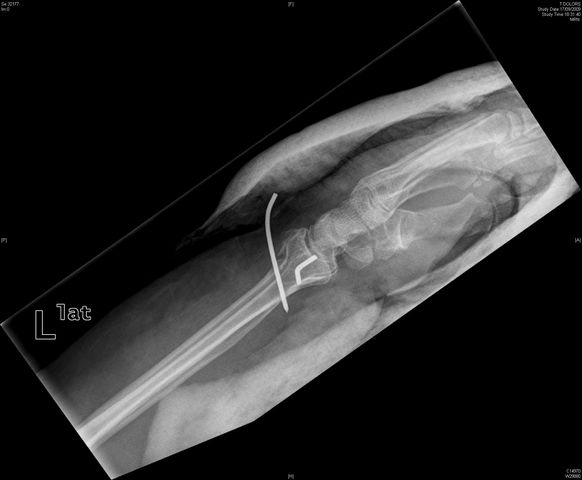

Fractura supracondílea de codo.

Fractura supracondílea de codo.Tras reducción y osteosíntesis.

Fractura supracondílea de codo. Tratamiento con agujas.